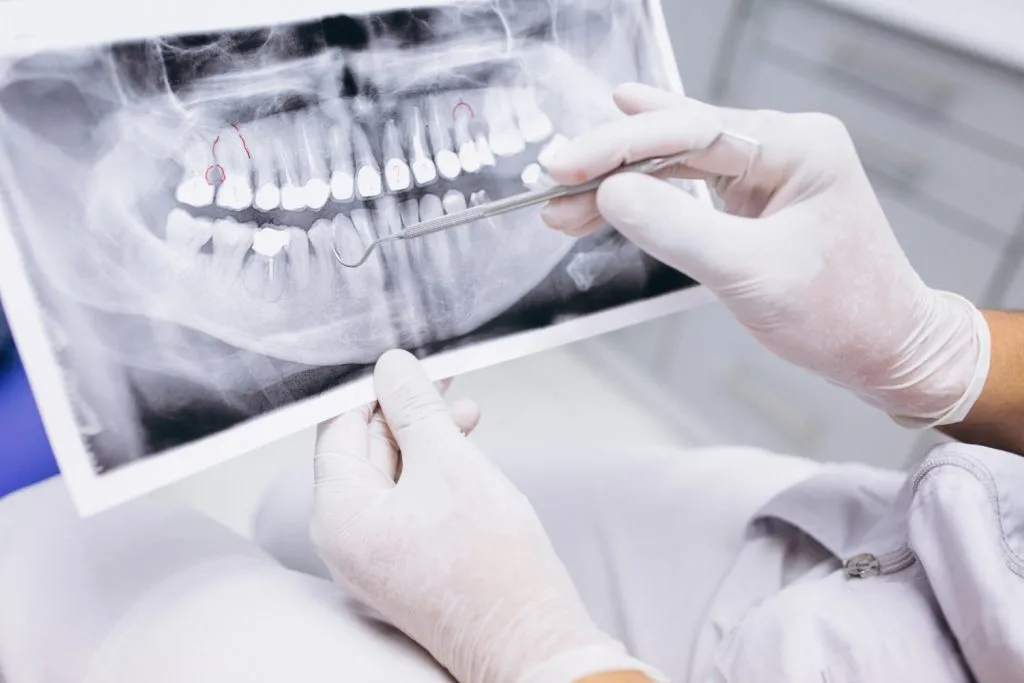

Dental X-rays: Types & Risks

What are the Common Types of Dental X-rays?

The two main types of X-rays in dentistry are intraoral and extraoral X-rays. Intraoral X-rays refer to when the X-ray film is in the mouth. Extraoral X-rays have a film outside the mouth.